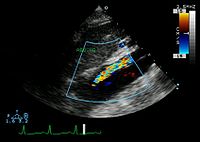

The transesophageal echocardiogram (TEE) is a good test in the diagnosis of aortic dissection, with a sensitivity up to 98% and a specificity up to 97%. It has become the preferred imaging modality for suspected aortic dissection. It is a relatively noninvasive test, requiring the individual to swallow the echocardiography probe. It is especially good in the evaluation of AI in the setting of ascending aortic dissection, and to determine whether the ostia (origins) of the coronary arteries are involved. While many institutions give sedation during transesophageal echocardiography for added patient comfort, it can be performed in cooperative individuals without the use of sedation. Disadvantages of TEE include the inability to visualize the distal ascending aorta (the beginning of the aortic arch), and the descending abdominal aorta that lies below the stomach. A TEE may be technically difficult to perform in individuals with esophageal strictures or varices.

Type A aortic dissection[23]